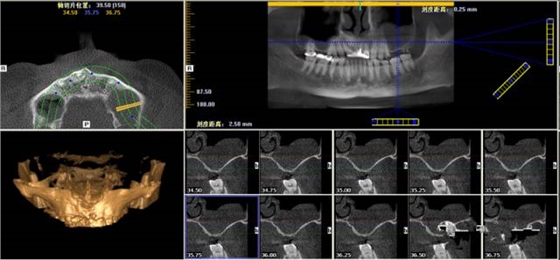

第二圖:上頜竇氣化,導(dǎo)致上頜竇很大,骨高度不足,但是上頜竇底平,粘膜很干凈。適合外提升或者高手可行內(nèi)提升。(還有二次內(nèi)提升)。